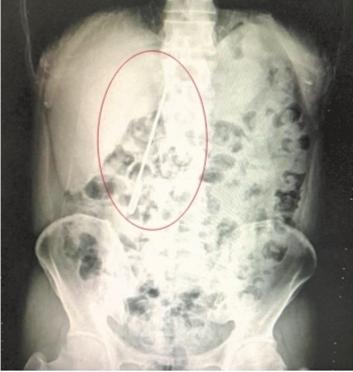

常先生腹中的毛衣针清晰可见

CT显示,毛衣针在常先生十二指肠拐弯处已穿透肠壁,,外露,有进一步损伤大血管及结肠的风险。医生立即为常先生实施手术,切开胃部取出毛衣针,并修补好十二指肠破口。